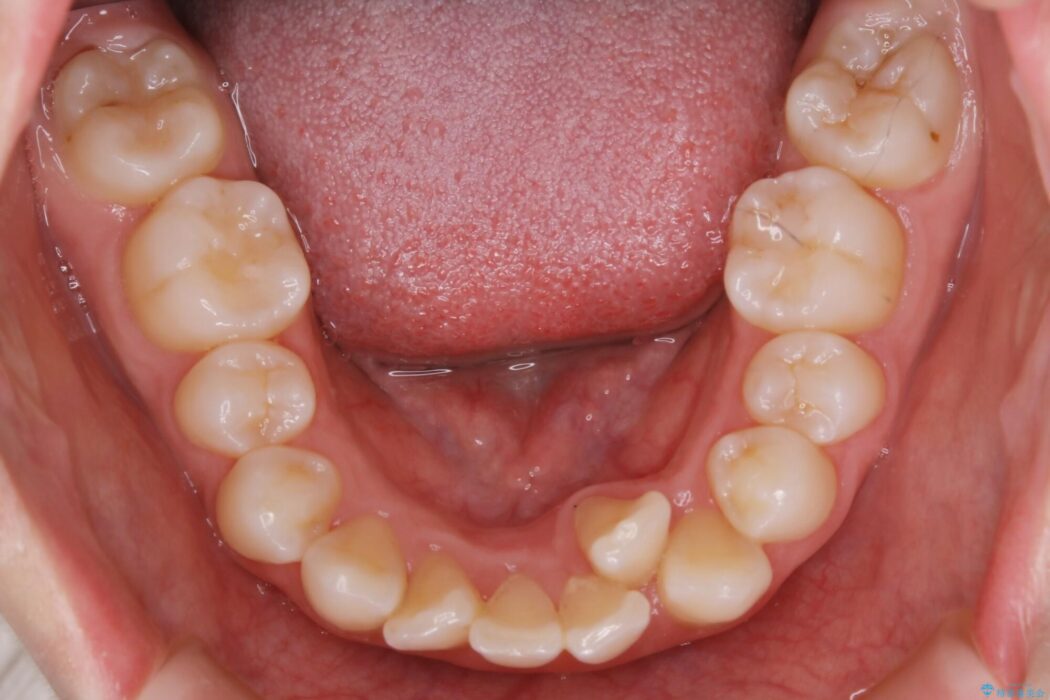

検査したところ歯に対して骨が上顎・下顎共に小さいことがわかりました。

それによりスペースが少なく歯列がガタついたり前方傾斜する生え方となっていました。

本症例の患者様は顎の骨が小さく歯をきれいに並べるための隙間がないため、歯が重なったり傾斜してしまっていました。

抜歯を行うことによりスペースを確保し、小さい骨幅でも歯並びを整えることができます。